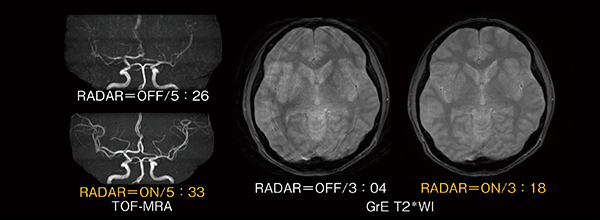

今回,TOFシーケンスおよびGrE(gradient echo)シーケンスに対応し,頭部ルーチン検査で必要な全シーケンスでRADARが併用可能な“All Round RADAR”となった。

RADARによるTOF-MRAとGrE T2*WIの画像例を図6に示す。これは意図的に動きを与えた状態での画像であるが,RADARの適用により,頭部血管の末梢まで明瞭に描出されている。

図6 RADAR画像例